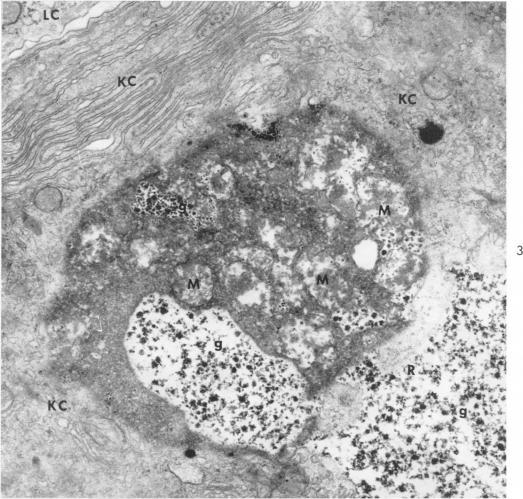

Electron Microscopic Observations on Councilman-Like Acidophilic Bodies and Other Forms of Acidophilic Changes in Human Liver Cells.

Biava C, Mukhlova-Montiel M

Am J Pathol. 1965 May;46(5):775-802.